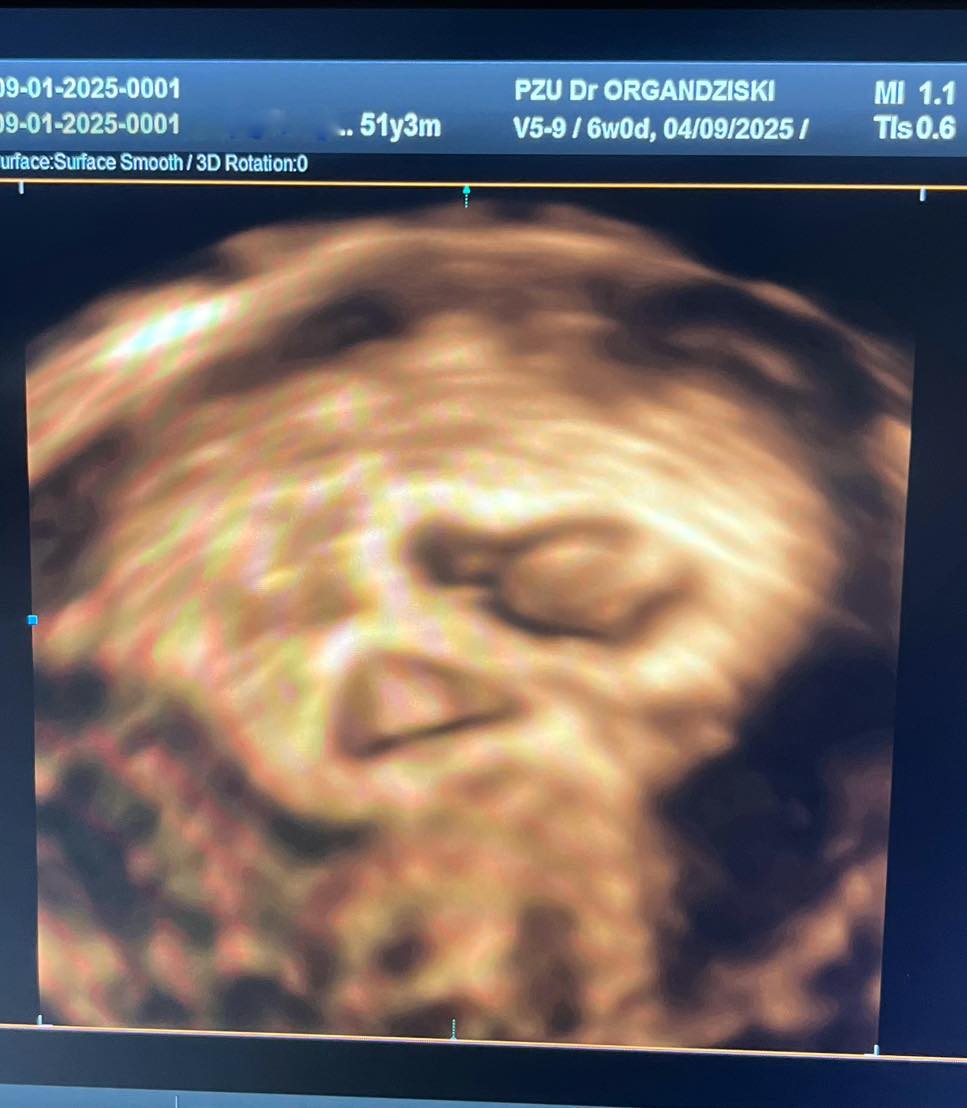

Годините се само бројка за исполнување на сонот! Не постојат препреки за нашиот тим од ИВФ Одделот и пишуваме уште еден голем успех!

Пациентката има две неуспешни ин витро процедури во други клиники, една со сопствени и една со донирани ооцити.

Во нашата болница постигнавме бременост со алогенеичко БПО со два ембриони!